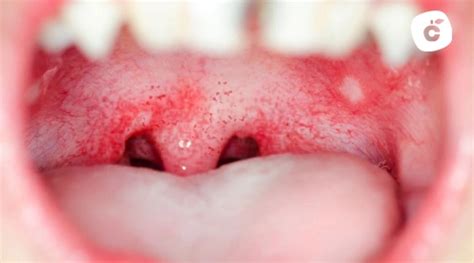

- Herpes: El herpes es un virus que una vez que se contrae ya no sale del organismo. Los herpes pueden aparecer en el cielo de la boca y estos, a diferencia de las llagas, son contagiosos y se identifican por su color rojizo. Por lo que es un virus que se manifiesta varias veces al año, sobre todo cuando la persona se encuentra en situaciones de estrés.

Las infecciones herpéticas forman parte del grupo de enfermedades infecciosas más frecuentes de la mucosa oral. Las enfermedades de la mucosa oral pueden ser causadas por distintos serotipos del virus del herpes humano (VHH). Los VHH son virus ADN bicatenarios. Se replican en la célula huésped y provocan en ella efectos citopáticos directos así como daños celulares por la inflamación inducida.

Después de la primoinfección, el virus llega por vía retrógrada a través de los axones a los ganglios nerviosos regionales y permanece allí en estado latente. La reactivación puede ser espontánea o ser el resultado de una diversidad de factores (tensión psíquica, fiebre, alteraciones hormonales, inmunosupresión, luz UV) y se observa en alrededor de un 40% de los infectados por el VHS. La recidiva se puede manifestar en todo el territorio de inervación del nervio trigémino, pero las localizaciones más frecuentes son el margen labial (herpes simple labial) o la zona perioral, y con menor frecuencia la mucosa nasal o el resto del rostro.

Las lesiones intraorales aparecen sobre todo en pacientes inmunodeprimidos y se localizan habitualmente en las encías y también en el paladar duro. Los pródromos de las lesiones clínicas visibles consisten en prurito, hormigueo y sensación de quemazón. A continuación se desarrollan pápulas rojizas agrupadas que se transforman en vesículas con un borde rojizo y que, por último, se ulceran y cicatrizan formando una costra.

Se prescindirá de todo tipo de intervención odontológica hasta que la enfermedad no haya avanzado a la fase de costras debido al riesgo de provocar una sepsis por virus del herpes. El dolor suele persistir durante aproximadamente 4 a 5 días y la curación en el paladar duro requiere unos 8 a 10 días. En pacientes inmunodeprimidos a consecuencia de cánceres o tratamientos inmunosupresores, en pacientes sometidos a radioterapia, a trasplantes o con infección por el VIH pueden observarse evoluciones clínicas anormalmente graves.